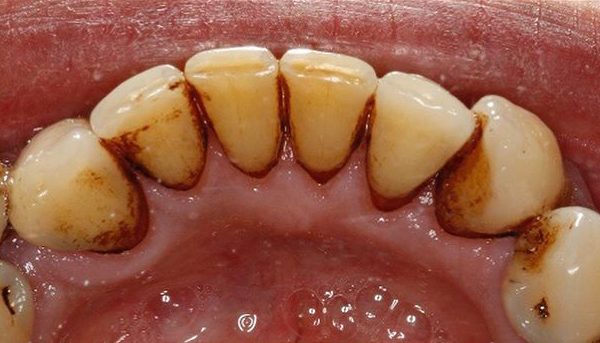

- Remove staining and discolouration caused by smoking or by drinking drinks such as red wine, tea and coffee etc

- Thoroughly remove dental plaque

Before and After Photos